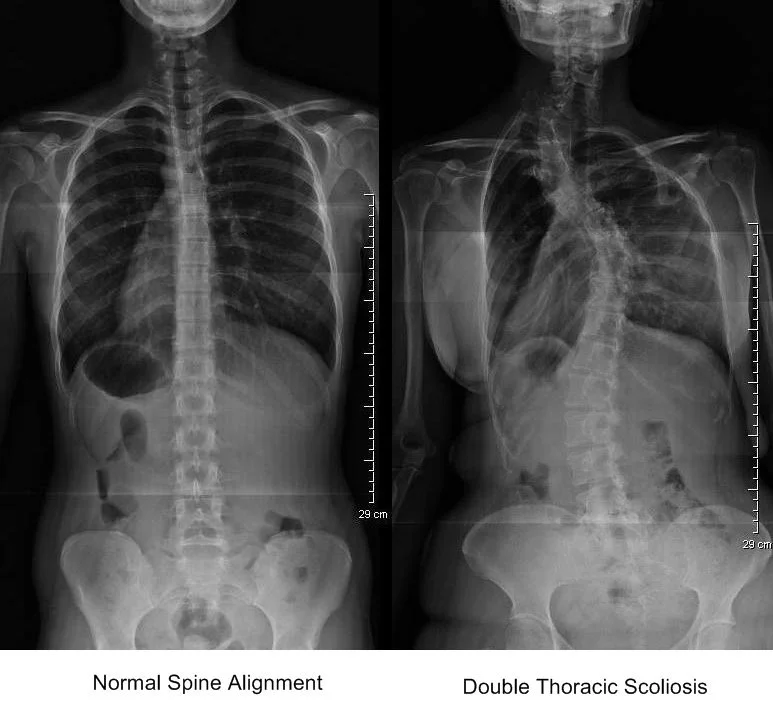

What is Scoliosis and How to treat? ACC